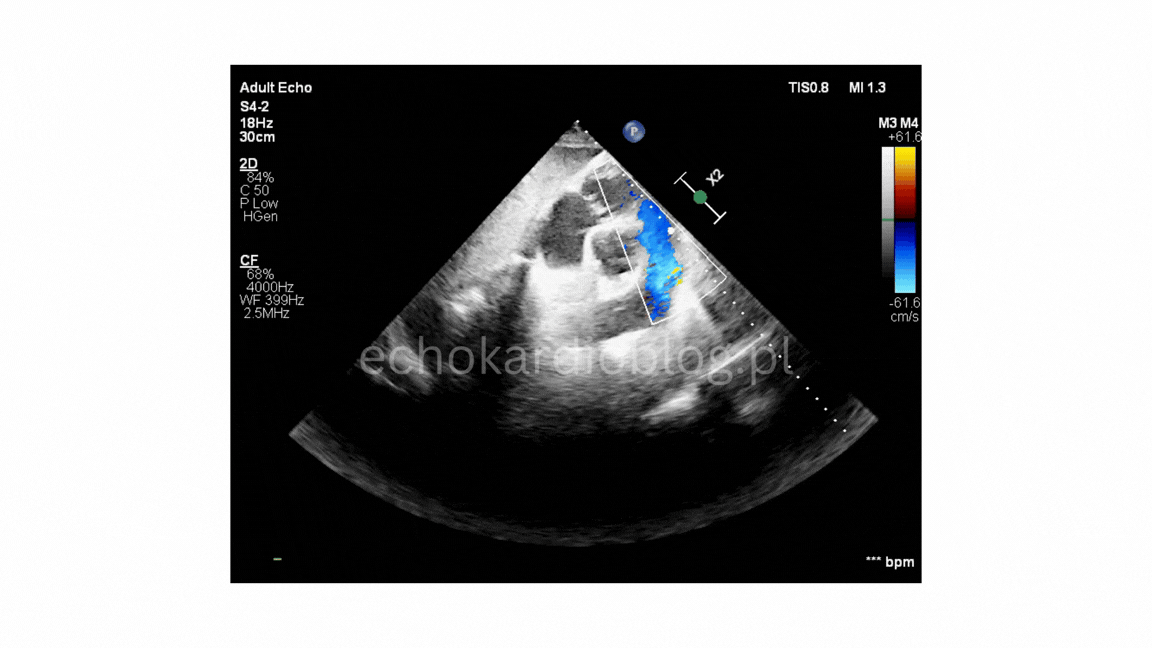

projekcja podmostkowa 4 jamowa- umiarkowana niedomykalność trójdzielna

ciężka niedomykalność płucna w projekcji podmostkowej